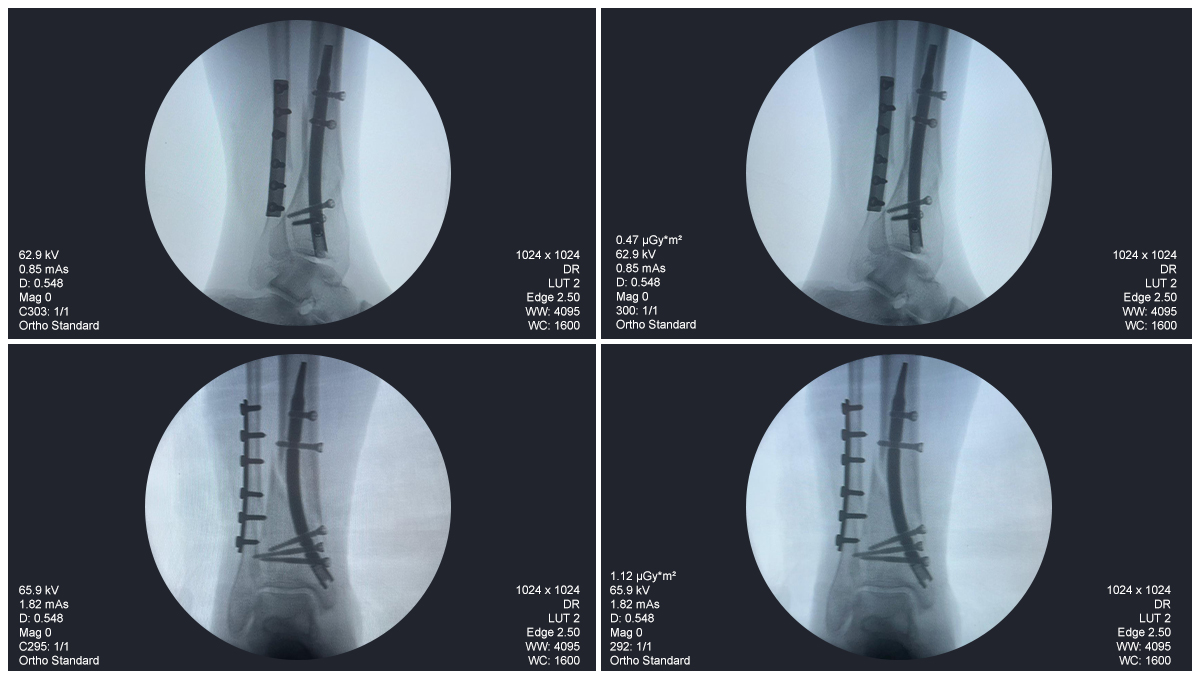

Radioscopie peropératoire de l'arceau, vues AP et latérales

Ce cas concernait une fixation tibiale distale à l’aide d’un clou tibial distal intramédullaire. La radioscopie peropératoire a confirmé la position du clou, des vis de verrouillage distales et de la fixation par plaque fibulaire.

Clou-tibial-distal-fluoroscopie-peropératoire-czmeditech (2)

Clou-tibial-distal-fluoroscopie-peropératoire-czmeditech (3)

Clou-tibial-distal-fluoroscopie-peropératoire-CZMEDITECH (4)

fluoroscopie-peropératoire-clou-tibial-distal-CZMEDITECH